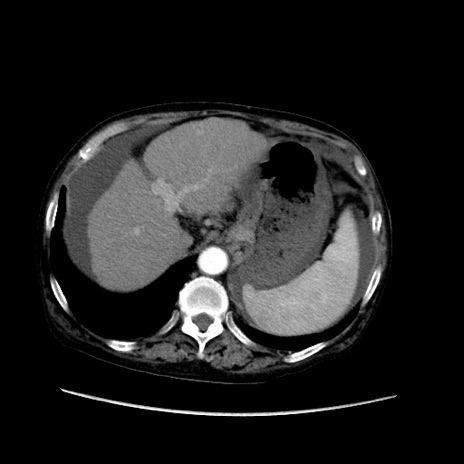

症例31(横断像)

【症例】80歳代 女性

【主訴】腹部膨満感

【現病歴】他院にて肝硬変にてフォロー中。1週間前から便秘、腹部膨満感、臍部腫瘤あり受診となる。

【既往歴】肝硬変

【身体所見】腹部膨隆あり、皮膚変化なし、疼痛なし。

【データ】WBC 4600、CRP 0.25